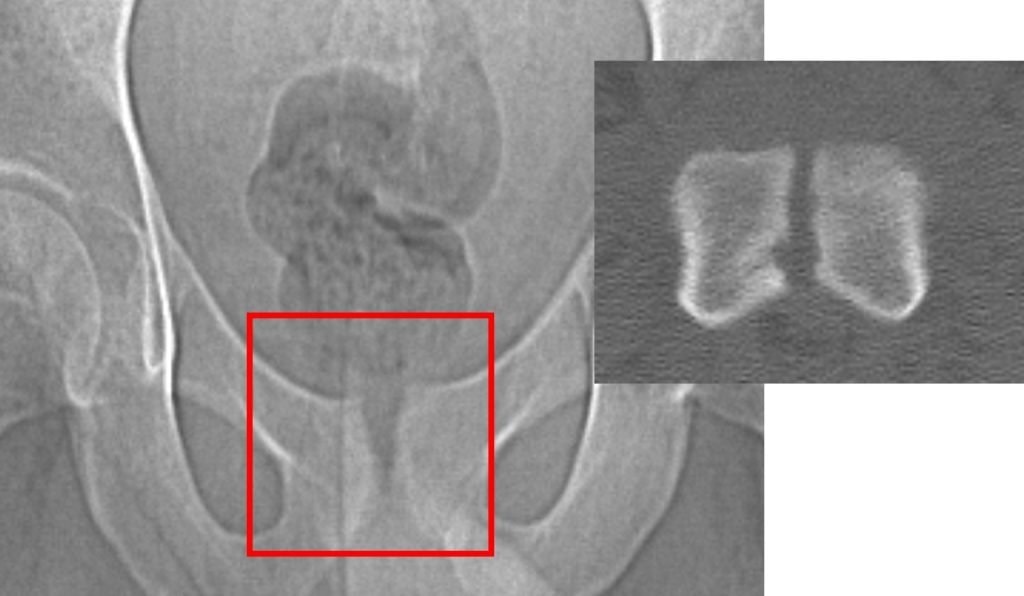

The images below, taken several months after the orthobiologic procedure, demonstrate significant improvement in the condition of the symphysis pubis joint.

The follow-up images indicate a restored joint space in the symphysis pubis, with improvements in the surrounding bone structure. The patient reported noticeable improvement, noting that 80–90% of his symptoms had diminished and that he experiences minimal daily discomfort. This outcome illustrates the potential role of orthobiologic procedures in supporting joint health and function.